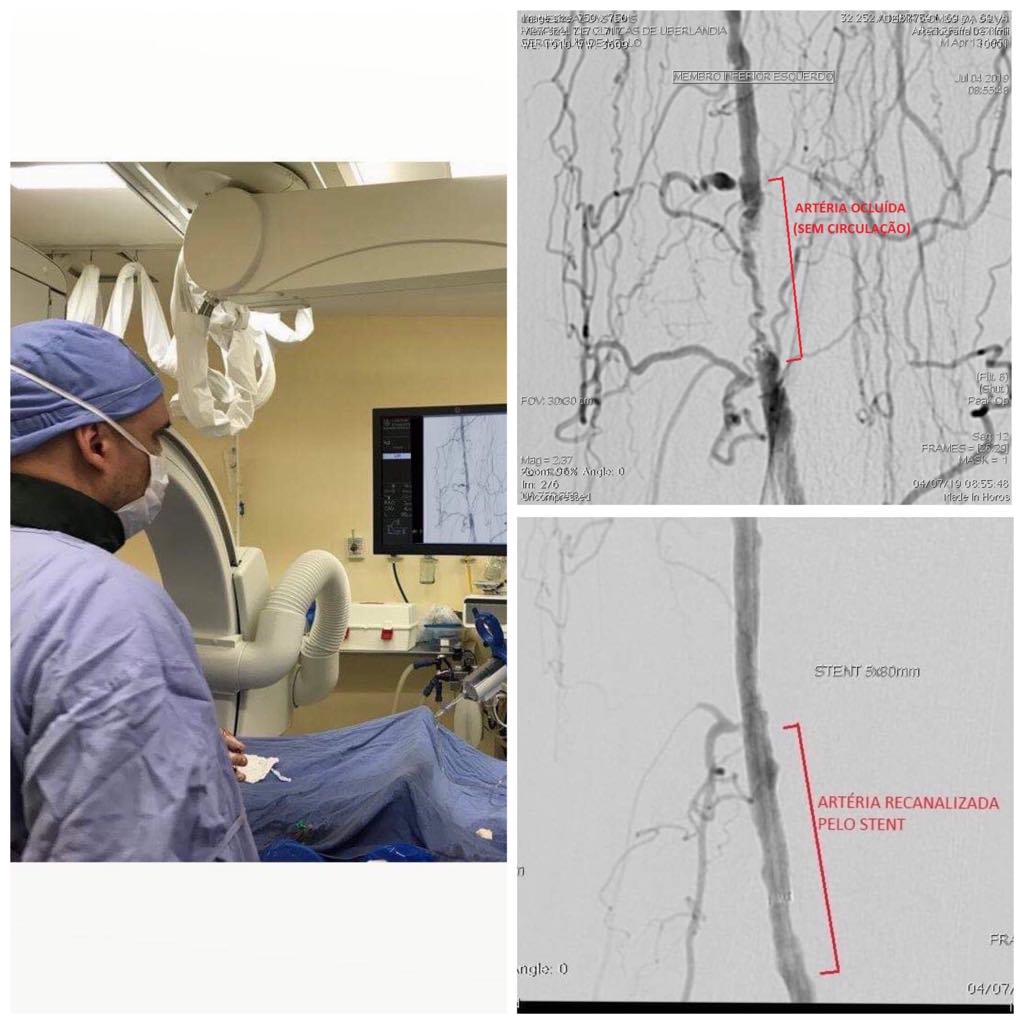

A Angioplastia é um procedimento usado em pacientes com a DAOP, que resulta em estreitamentos (estenose), ou oclusões completas das artérias. Consiste na dilatação mecânica de qualquer vaso estreitado ou obstruído por meio de um cateter de balão ou um stent metálico, se necessário.  Os angiógrafos, conhecidos como “aparelhos de hemodinâmica”, permitem visualizar com detalhes os vasos ao orientar cateteres especiais até o local da lesão, para se promover a dilatação e a correção da obstrução.

Em muitos casos, no  procedimento, é feito o implante de um stent, dispositivo metálico de formato tubular, capaz de manter o vaso sanguíneo aberto e com bom funcionamento , objetivando o salvamento do membro ou órgão acometido, de uma gangrena e disfunção respectivamente, e minimiza o risco de novas obstruções no futuro.